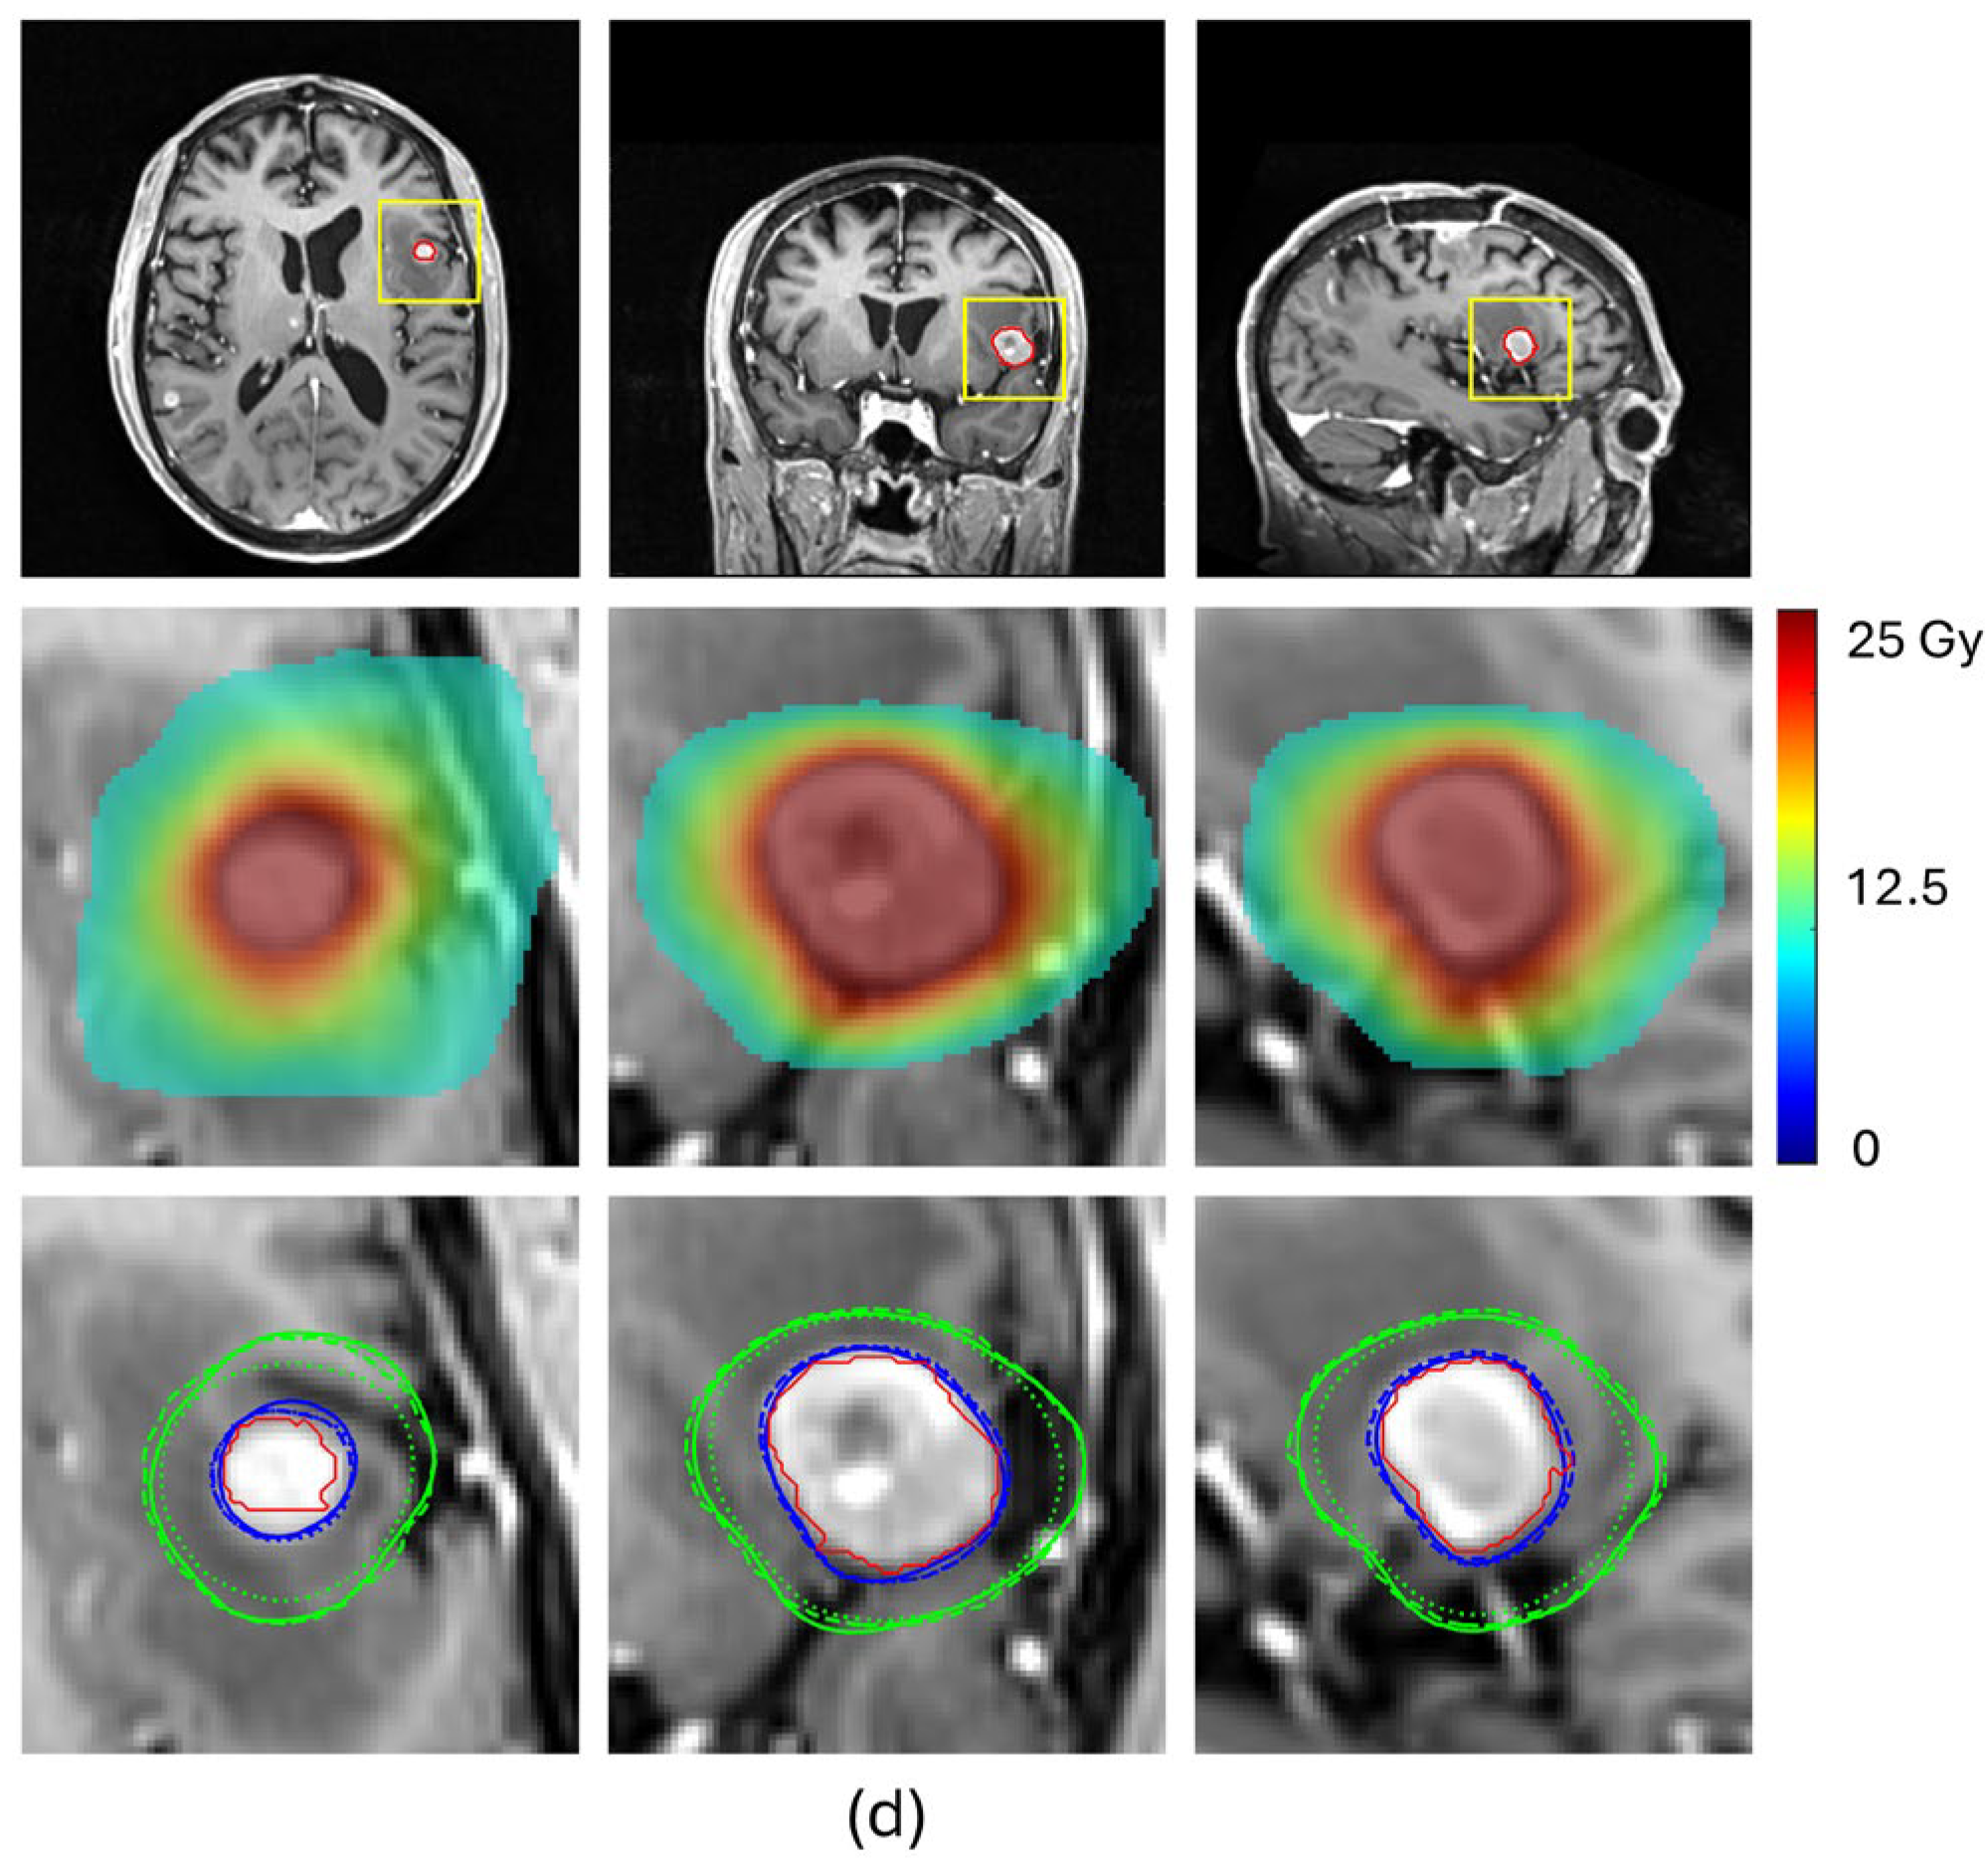

Table 2 and Figure 4 compare the prediction performance of our proposed method with a baseline HD-U-Net trained using the conventional MSE loss for four representative BMs, each selected from a different volume group. For the two small-volume BMs, BM 1 and BM2, our method achieved substantially higher DSC values for both 100% and 50% isodose lines (DSC100%: 0.908 vs. 0.790 for BM1 and 0.936 vs. 0.886 for BM2, DSC50%: 0.947 vs. 0.849 for BM1 and 0.908 vs. 0.827 for BM2), indicating markedly improved agreement with the ground truth dose distribution (Figure 4a,b). These gains translated into significant improvements in plan quality prediction. Selectivity error decreased from 0.19 to 0.06 for BM1 and from 0.11 to 0.06 for BM2, CI50 error reduced from −5.04 to −1.55 for BM1 and from −3.05 to −1.75 for BM2, and GI error from 0.91 to 0.56 for BM1 and from −0.53 to −0.27 for BM2. For the mid-volume BM3, while the baseline mode already produced reasonable similarity in the 100% isodose line, our method further improved the DSC value from 0.926 to 0.944, reducing selectivity error from 0.10 to 0.06. More notably, our method significantly increased the DSC value of the 50% isodose line from 0.847 to 0.925, consistent with the isodose lines shown in Figure 4c, reducing CI50 error from −1.25 to −0.40. With both isodose lines improved, the GI error decreased from −0.48 to −0.01. For the large-volume BM4, both methods achieved comparable similarity for the 100% isodose line (DSC100%: 0.952 vs. 0.951), while our method produced a higher DSC for the 50% isodose line (DSC50%: 0.951 vs. 0.912), as illustrated in Figure 4d. This improvement translated to a decrease in the CI50 error from −0.50 to 0.25 and the GI error from −0.63 to less than 0.01. These results demonstrate that our proposed method consistently enhances similarity of the 100% and 50% isodose lines of the predicted doses relative to those of ground truth doses, especially for small-volume lesions, leading to more accurate prediction of plan quality metrics.

Figure 4. Subfigures (ad) show the predicted results for the four representative BMs, respectively. In each subfigure, the first row displays MRI images in transverse, coronal and sagittal views, with the BM contour outlined in red; The second row presents a zoomed-in view of the BM region (as indicated by the rectangle in the first row), showing the ground truth dose distribution in color wash; The third row compares 100% isodose lines (yellow) and 50% isodose lines (green) from the ground truth dose distribution (solid lines), the dose predicted by the HD-U-Net trained with conventional MSE loss (dotted lines), and the dose predicted by the HD-U-Net model trained with our proposed method (dashed lines).